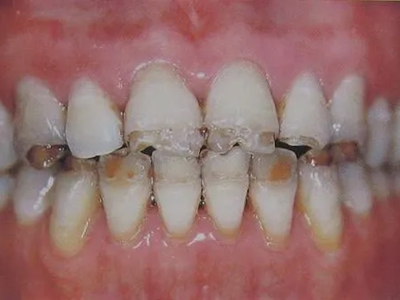

牙釉质发育不全牙表面上有坑图

牙釉质发育不全发展到严重时,导致牙釉质表面缺损,表现为带状、窝状的褐色凹坑,容易积存食物残渣诱发龋齿,表现为牙齿边上出现深褐色小洞。